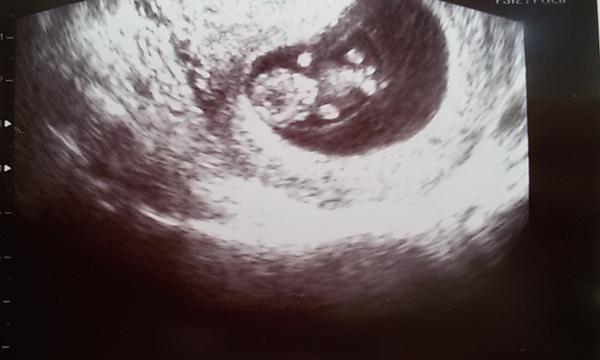

prsa a zvetsuji se..Druhy den mi bylo zase dobre, akorat me pichalo v podbrisku, ale trosku jinak nez obvykle..bodava bolest. Druha carka zesilila, ted v pondeli mi udelal Mudr. test z krve a hcg mam 518..za tyden mam jit na utz 🙂